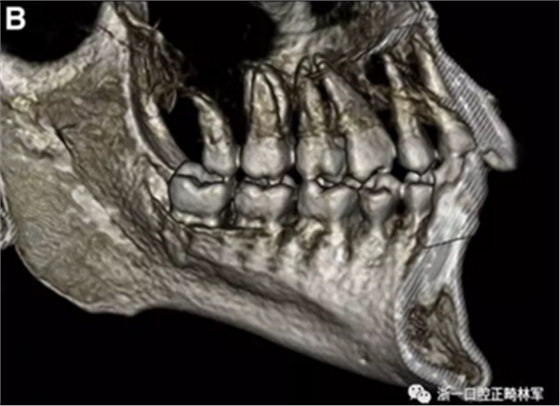

患者的上頜骨和下頜骨研究模型在最大牙尖交錯位時確定和數(shù)字化(圖2,A),作為咬合指導(咬合指導)。該數(shù)字化咬合指導在齦緣周圍進行數(shù)字化修剪,以便在CBCT掃描上可以更好得可視化(圖2,B)。

圖2. A,咬合時對象研究模型的右側(cè)舌側(cè)視圖掃描將作為未來指導;該指導稍后用于將懸浮的下頜骨配對到修剪的上頜骨;B,左側(cè)舌側(cè)視圖的數(shù)字化修整牙合引導。